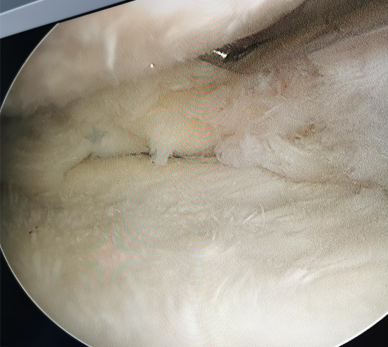

关节镜是近年来发展起来的一种关节微创手术。用于关节内疾病的检查、诊断和治疗。膝关节镜的外形很像一支铅笔,直径只有5~6mm粗细。在皮肤上做一个6~8mm的小切口,就可以把关节镜放入关节内。通过关节镜的后方连接的微型摄像系统,就可以把关节内的情况清晰地显示在电视荧光屏上。经关节镜可以仔细观察关节内的情况,直接准确地发现病变的部位,并立即在关节镜的观察下通过刨削打磨系统和专用器械进行手术,不需要额外再做大切口。膝关节镜手术已成为关节外科工作中的重要检查诊断方法和治疗手段。

由于关节镜几乎可以看到关节内所有的部位,因此比切开关节看的更全面;图像经过放大,比切开关节看得更准确;切口很小,创伤小,疤痕少,康复快,并发症少。多数患者术后第二天即可下地活动,术后三天即可出院膝关节结构复杂,功能特殊,负重大,受伤几率较高且不易恢复。

膝关节内的软骨结构、滑膜、半月板、韧带和关节面的损坏在X线片上往往难以发现,但在关节镜下却一目了然。原则上,任何膝关节内的病变都是膝关节镜的手术适应症。

半月板损伤修补术